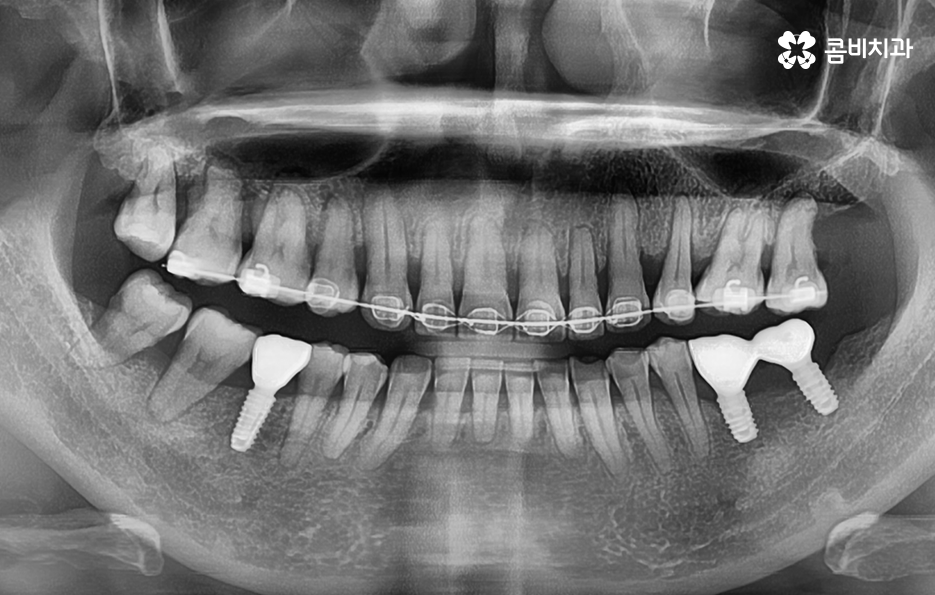

오늘 보시는 포스팅에서의 치료 과정도 어금니에 임플란트가 필요한 상태에서 윗니를 보시면 윗니가 다소 벌어진 것을 확인할 수 있는데요. 교정 하면 보통 전체교정을 떠올리게 되긴 하지만 경우에 따라서는 치열이 전체적으로 가지런한 편인데 앞니가 살짝 벌어진 경우나 어금니만 다소 벌어진 경우도 있을 거예요

이러한 경우에는 부분교정을 통해서 다소 개선이 필요한 치열을 가지런하게 만들고 가지런해진 치열과 교합 상태에 적합한 임플란트 치료 계획을 세워서 치아의 심미성과 기능적인 부분, 얼굴과의 조화를 종합적으로 고려하여 좋은 결과를 얻을 수 있어요

임플란트는 잇몸 뼈에 고정이 되어 있기 때문에 돌출입 교정과 같이 치아의 이동이 많은 경우에는 어렵지 않을까 생각하시는 분들도 많을 거예요. 임플란트를 한 상태에서 돌출입 교정과 같은 치료를 한다고 가정할 때 어금니에 임플란트를 한 경우에는 임플란트를 오히려 고정원으로 써서 앞니를 안으로 당기는데 활용할 수 있어요

앞니에 임플란트를 한 경우에는 자연치아를 모두 안쪽으로 움직이게 한 후에 앞니 임플란트 보철물만 새롭게 제작하여 치아교정을 마무리하는 방법도 있어요